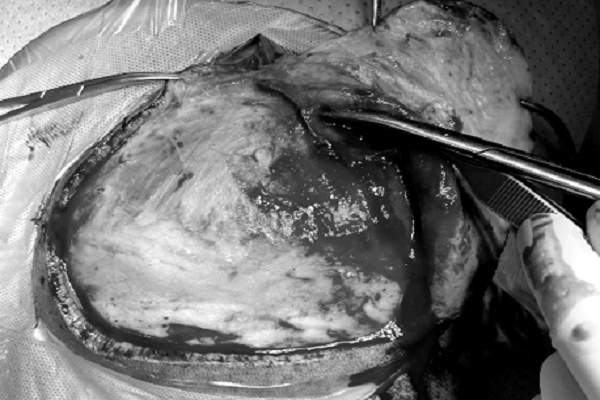

Ê kíp phẫu thuật Bệnh viện Quân y 175 tiến hành mổ mở sọ giải áp khẩn cấp

Trước nguy cơ tử vong cận kề, ê kíp ngoại thần kinh buộc phải tiến hành mổ mở sọ giải áp khẩn cấp. Trong quá trình phẫu thuật, các bác sĩ phát hiện động mạch thái dương bị tắc hoàn toàn bởi các tế bào mỡ. Kết quả giải phẫu bệnh sau đó xác nhận chẩn đoán thuyên tắc mỡ, củng cố nguyên nhân trực tiếp từ thủ thuật thẩm mỹ trước đó.

Ca mổ kéo dài trong điều kiện áp lực cao đã giúp giải phóng chèn ép não, đưa bệnh nhân vượt qua giai đoạn nguy kịch. Sau 13 ngày điều trị hồi sức, bệnh nhân dần tỉnh lại và được chuyển ra khỏi khoa hồi sức tích cực.